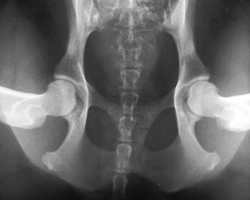

The PennHIP method is a novel way to assess, measure and interpret hip joint laxity. It consists of three separate radiographs: the distraction view, thecompression view and the hip-extended view. The distraction view and compression view are used to obtain accurate and precise measurements of joint laxity and congruity. The hip-extended view is used to obtain supplementary information regarding the existence of osteoarthritis (OA) of the hip joint. (The hip-extended view is the conventional radiographic view used to evaluate the integrity of the canine hip joint.) The PennHIP technique is more accurate than the current standard, and it has been shown to be a better predictor for the onset of OA.

The radiographs pictured here are of the same dog, yet the hip joint laxities in each view look very different. Notice that the hips in the distraction view appear to be much looser than they do in the hip-extended view.

Distraction View Compression View Hip-Extended View

The looser the joint on the distraction view, the greater is the chance that the hip will develop OA. The hip-extended view tends to mask true hip joint laxity because the joint capsule is wound up into a tightened orientation when the hips are extended. This explains why measurable joint laxity on the distraction view is always greater than the measurable laxity from the hip-extended view. In fact, distraction laxity is up to 11 times greater depending on the breed of dog under study.

The compression view is used to determine the "goodness of fit" of the femoral heads into the acetabula. In a hip with OA, the remodeling that occurs in the acetabulum and/or the femoral head, will often result in an ill-fitting "ball" and "socket".